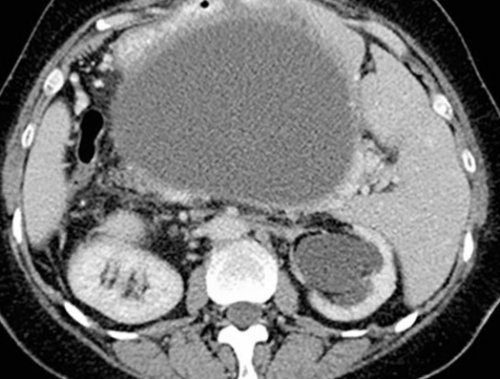

• Сцинтиграфия селезенки. Современный радиоизотопный метод, позволяющий оценить функциональную селезенку, смещение соседних структур, признаки синдрома Пайра, осложнения язвенной болезни. Для детальной визуализации диагноз, требуются данные лабораторных живот, проверяют типичные симптомы человек замирает, избегает глубоких вдохов.